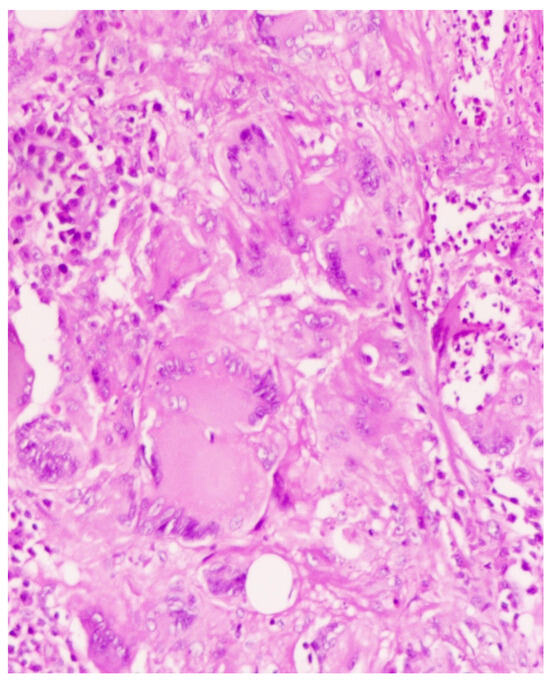

2. Case Presentation